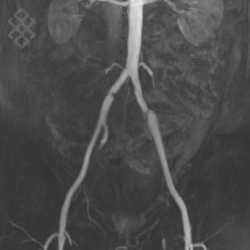

Angio-IRM des Membres inférieurs

Pour une angio-IRM des membres inférieurs, aucune préparation n'est requise. Dans le cas d'une injection du produit de contraste, un cathéter vous sera posé par le personnel soignant. De même, en fonction de votre âge, le centre vous prescrira une prise de sang pour évaluer le taux de créatinine.

Vous entrez dans l'aimant, ouvert des 2 côtés, les pieds en premier et allongé sur le dos. Pour recueillir le signal et construire les images, vous aurez une antenne sur l'abdomen. Étant donné que cet examen est bruyant, vous aurez à votre disposition des tampons auriculaires pour atténuer le bruit de la machine.

La durée moyenne de l'examen est de 30 min. Dans le cas d'une injection, le manipulateur en radiologie vous administrera le produit de contraste. Vous entendrez un bruit caractéristique à l'IRM faisant penser à un marteau piqueur.